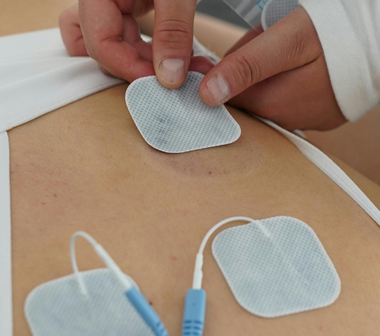

Eletroacupuntura

Como funciona: Utiliza correntes elétricas de baixa frequência para estimular os pontos de acupuntura através das agulhas inseridas, proporcionando estímulos por longo tempo.

Objetivo: Obter analgesia em casos de dores agudas, como hérnias de disco, e para tratamentos cirúrgicos.